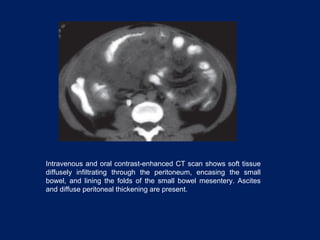

Intravenous and oral contrast-enhanced CT scan shows soft tissue

diffusely infiltrating through the peritoneum, encasing the small

bowel, and lining the folds of the small bowel mesentery. Ascites

and diffuse peritoneal thickening are present.